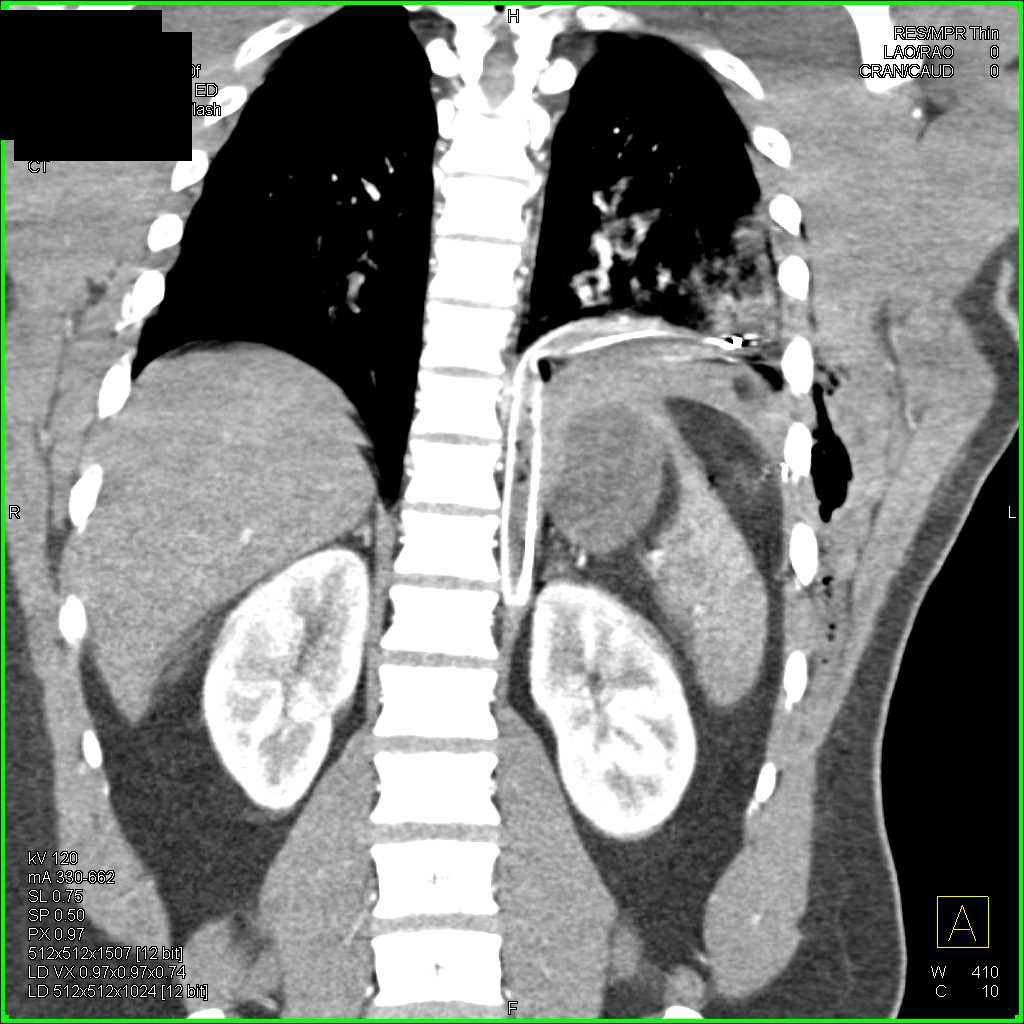

Trauma with Multiple Left Rib Fractures and Pulmonary Contusion Rib Fracture Lung Contusion Injury to the lung parenchyma can result from blunt or penetrating trauma mechanisms. This document provides a framework for the assessment and management of adult patients with rib fractures at imperial college healthcare nhs. Find out when to seek medical. We hypothesized that among patients with rib fractures, there is a stepwise increase in risk of pulmonary complications and mortality. Rib Fracture Lung Contusion.

From www.ctisus.com